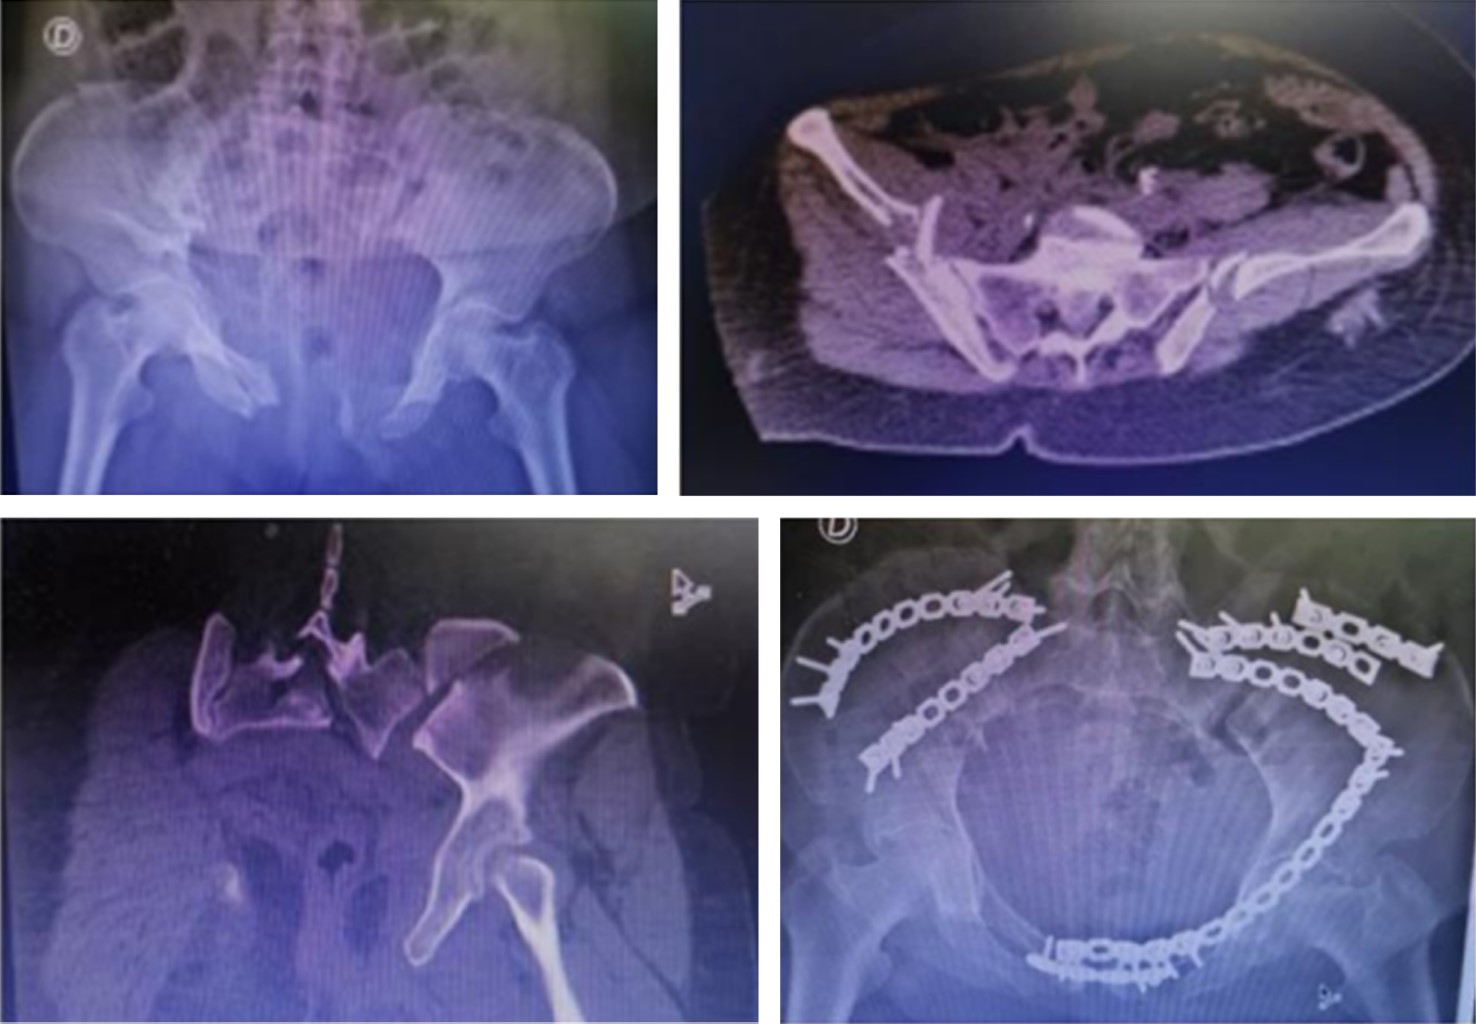

Muerte. Se registró una muerte de manera intrahospitalaria. Correspondió a una mujer de 77 años, hipertensa y portadora de fibromialgia, arrollada por vehículo automotor; sufrió fractura de pelvis asociada a acetábulo (Figura 2) con lesiones asociadas de hemotórax derecho, fracturas costales, ISS 20; fue reanimada siguiendo lineamientos del ATLS, requirió cirugía de control de daños (fijación externa) y fijación definitiva al cuarto día del ingreso, a través de abordaje ilioinguinal limitado bilateral (primera y tercera ventana). El deceso ocurrió tres días después por tromboembolismo pulmonar masivo en la Unidad de Cuidados Intensivos.